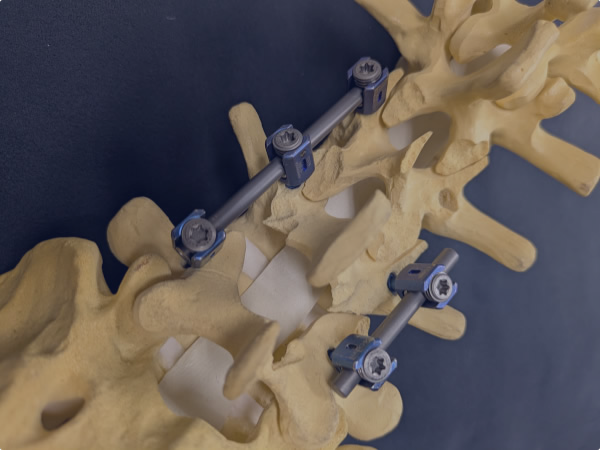

Our research focuses on metal-based crystalline materials. We aim to systematize materials design methods for advanced control of material properties that emerge from static and dynamic changes in atomic arrangements and microstructures. Through this approach, we pursue the development of new materials and the proposal of innovative processing techniques. In addition, we strive to accurately identify challenges and needs in clinical settings and work toward creating metal-based medical devices that provide functions tailored to those needs.